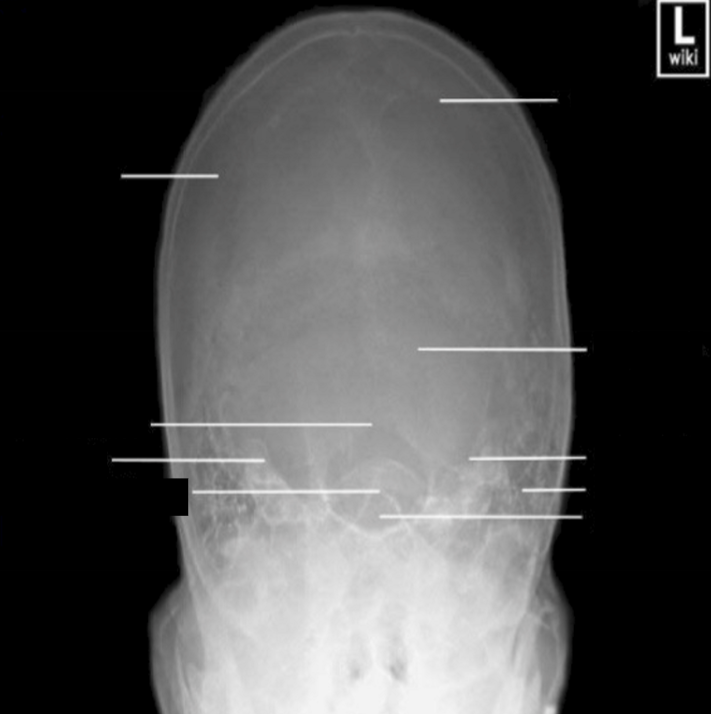

Please label